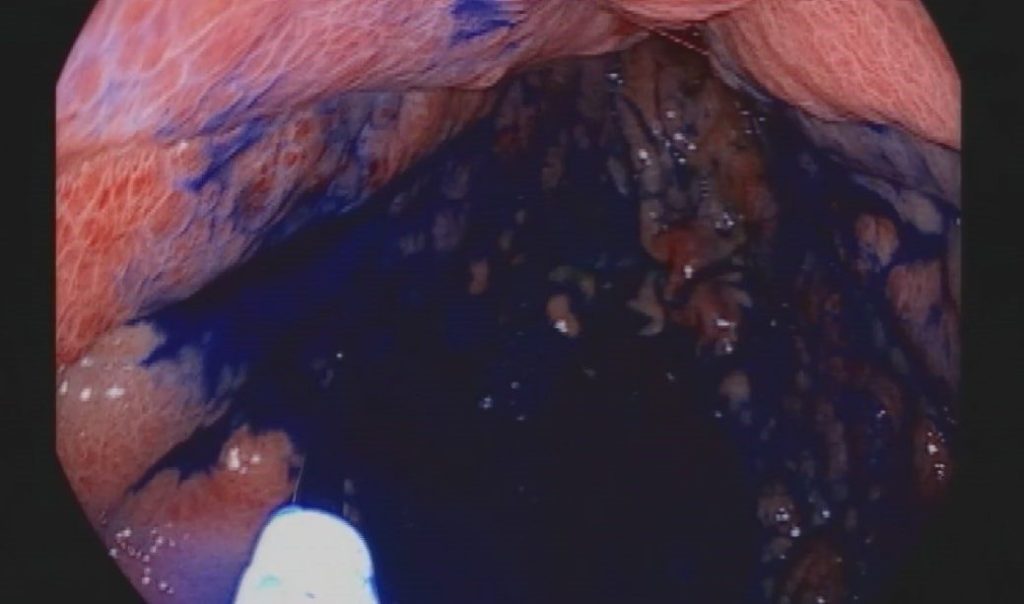

“Biz endoskopi yaparken, hem gastroskopi hem kolonoskopi yapıyoruz. Mide ve kalın bağırsak mukozasını özel boyalarla boyuyoruz. Bu işlem, normal mukoza ile kanserli hücre arasındaki farkı belirgin hale getiriyor. Çünkü endoskopide temel olan cerrahın ya da endoskopi yapan endoskopistin mukozayı çok iyi araştırması, ayrıntılı muayene etmesi, farklı olan bölgeleri yakalaması ve oradan biyopsi almasıdır. Ancak normal ışıklı endoskopilerle bunu yakalamak her zaman mümkün olmuyor. Bunu ancak kromoendoskopi dediğimiz boyama tekniği ile yakalamak mümkün hale geliyor. Endoskopik işlem sırasında boyayla mukozayı boyuyoruz. Burada kanserli ya da kanser öncesi hücreler, verdiğimiz bu boyayı az yakalıyor. Ardından aynı mukozayı yıkayıp tekrar bakıyoruz fakat bu tür kanserli hücreler yakalamış olduğu boyayı bırakmıyor. Mukoza eski pembe kırmızı halini alırken kanser hücreleri az da olsa tutmuş olduğu boyayı bırakmıyor. Bu farklı noktalardan biyopsi alıyoruz ve hastalığı erken yakalıyoruz.”

Boyama yöntemi ile mide ve bağırsak kanserinde erken teşhis